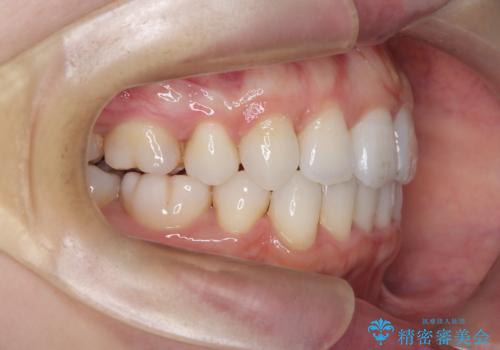

【抜歯インビザ】凸凹を綺麗になおしたい

- 前歯の凸凹を主訴に来院されました。

叢生量が多いため、抜歯が必要となるため、ワイヤー矯正をお勧めしましたが、患者さんの希望によりインビザラインで治療を開始しました。途中でワイヤーリカバリーを必要とせず終了でき患者さんには満足していただけました。